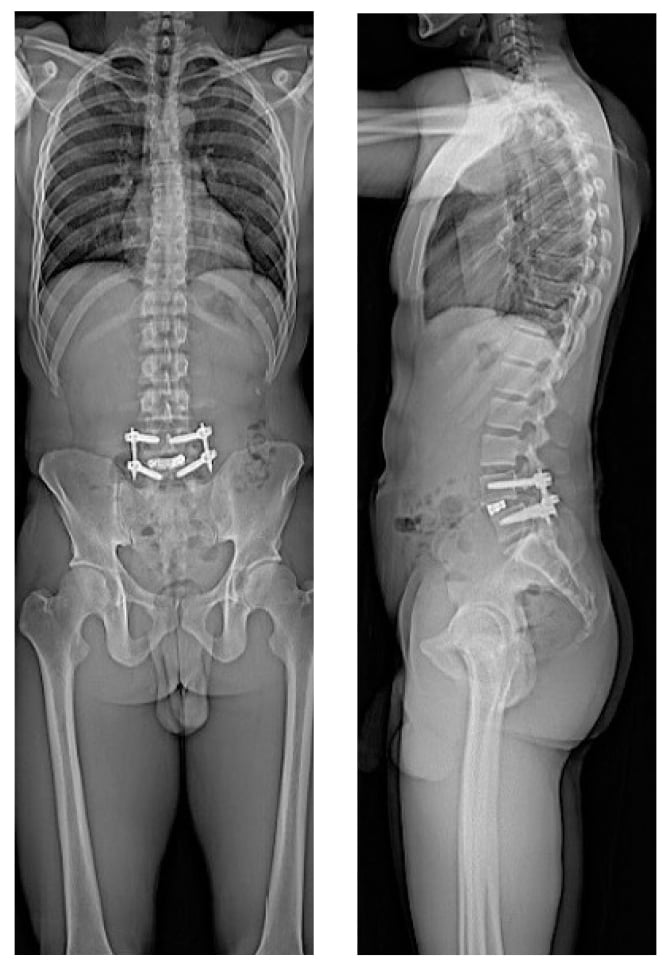

The patient underwent robotic assisted minimally invasive lumbar decompression and fusion with transforaminal lumbar interbody fusion (TLIF) cage placement. Intraoperatively, the patient was positioned prone and 3D Ziehm Vision (Ziehm Imaging) radiographs were obtained. Images were transferred to an Excelsius surgical robot (Globus Medical), and robotic planning was done intraoperatively for pedicle screw placement, tubular retractor placement, and interbody cage placement. First, percutaneous screws were placed in bilateral pedicles of L4 and L5. Muscle-sparing laminotomy, decompression, and L4–L5 discectomy were then performed via tubular retractor. Next, the interbody cage was trialed, placed, and packed with local and iliac crest bone autograft. Finally, rods were inserted percutaneously (Fig. 3).

Figure 3: Postoperative standing radiographs demonstrating re-established disc height and lumbar lordosis.